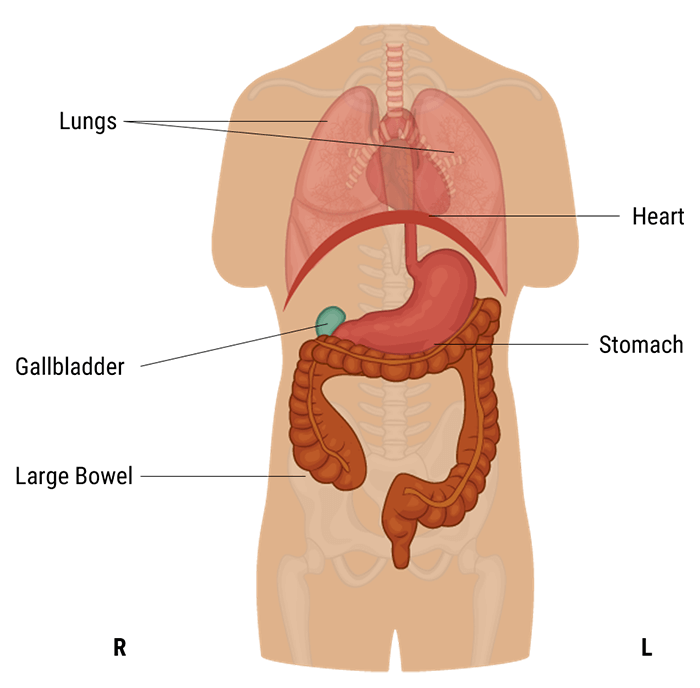

First, we shall know where is located the abdominal and pelvic cavity. The abdominal cavity is a large cavity found in the torso between thoracic pelvic cavities. It is separated from the thoracic cavity by the diaphragm.

A protective layer called the peritoneum, which plays a role in supporting organs, immunity, and fat storage, lines the abdominal cavity. As shown in this diagram, there is no overlapping partition between the pelvic and abdominal cavities.

Now let’s talk about the anatomy of the abdominal cavity and have a summary of the function of each organ.

The abdominal cavity is the largest body cavity in humans, it is lined by a thin, serous membrane called the peritoneum and contains different vital organs such as the liver, gallbladder, stomach, spleen, pancreas, kidneys, ureters, intestines, and the arterial and venous systems.

The stomach is a thick-walled digestive organ found on the left side of the abdomen. It is followed by the first portion of the small intestine, called the duodenum.

The Liver is the largest organ in the abdomen. It is located on the upper right side of it, right under the diaphragm. It has two lobes that are separated by a ligament. It plays a crucial role in our bodies as it maintains normal blood glucose levels, produces bile, and detoxifies the blood.

The Gall bladder is found below the liver and is connected to it. It stores and concentrates bile that is sent to the duodenum when needed for fat digestion and absorption.

Sthenic

A sthenic person is a muscular, thick-set individual similar to hypersthenic but not quite as broad in relation to height. The stomach and gall-bladder lie more vertically and the transverse colon curves lower.

Hyposthenic and sthenic patients have very similar organ placement. Little or no manipulation of the grid, milliamperage, source-to-image distance (SID), or kilovolts peak are needed because these technical factors are almost interchangeable for hyposthenic and sthenic patients.